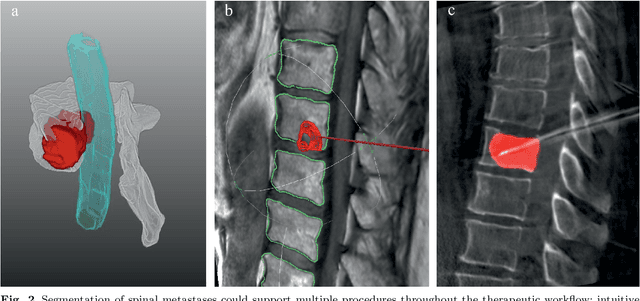

Abstract:This study's objective was to segment spinal metastases in diagnostic MR images using a deep learning-based approach. Segmentation of such lesions can present a pivotal step towards enhanced therapy planning and validation, as well as intervention support during minimally invasive and image-guided surgeries like radiofrequency ablations. For this purpose, we used a U-Net like architecture trained with 40 clinical cases including both, lytic and sclerotic lesion types and various MR sequences. Our proposed method was evaluated with regards to various factors influencing the segmentation quality, e.g. the used MR sequences and the input dimension. We quantitatively assessed our experiments using Dice coefficients, sensitivity and specificity rates. Compared to expertly annotated lesion segmentations, the experiments yielded promising results with average Dice scores up to 77.6% and mean sensitivity rates up to 78.9%. To our best knowledge, our proposed study is one of the first to tackle this particular issue, which limits direct comparability with related works. In respect to similar deep learning-based lesion segmentations, e.g. in liver MR images or spinal CT images, our experiments showed similar or in some respects superior segmentation quality. Overall, our automatic approach can provide almost expert-like segmentation accuracy in this challenging and ambitious task.